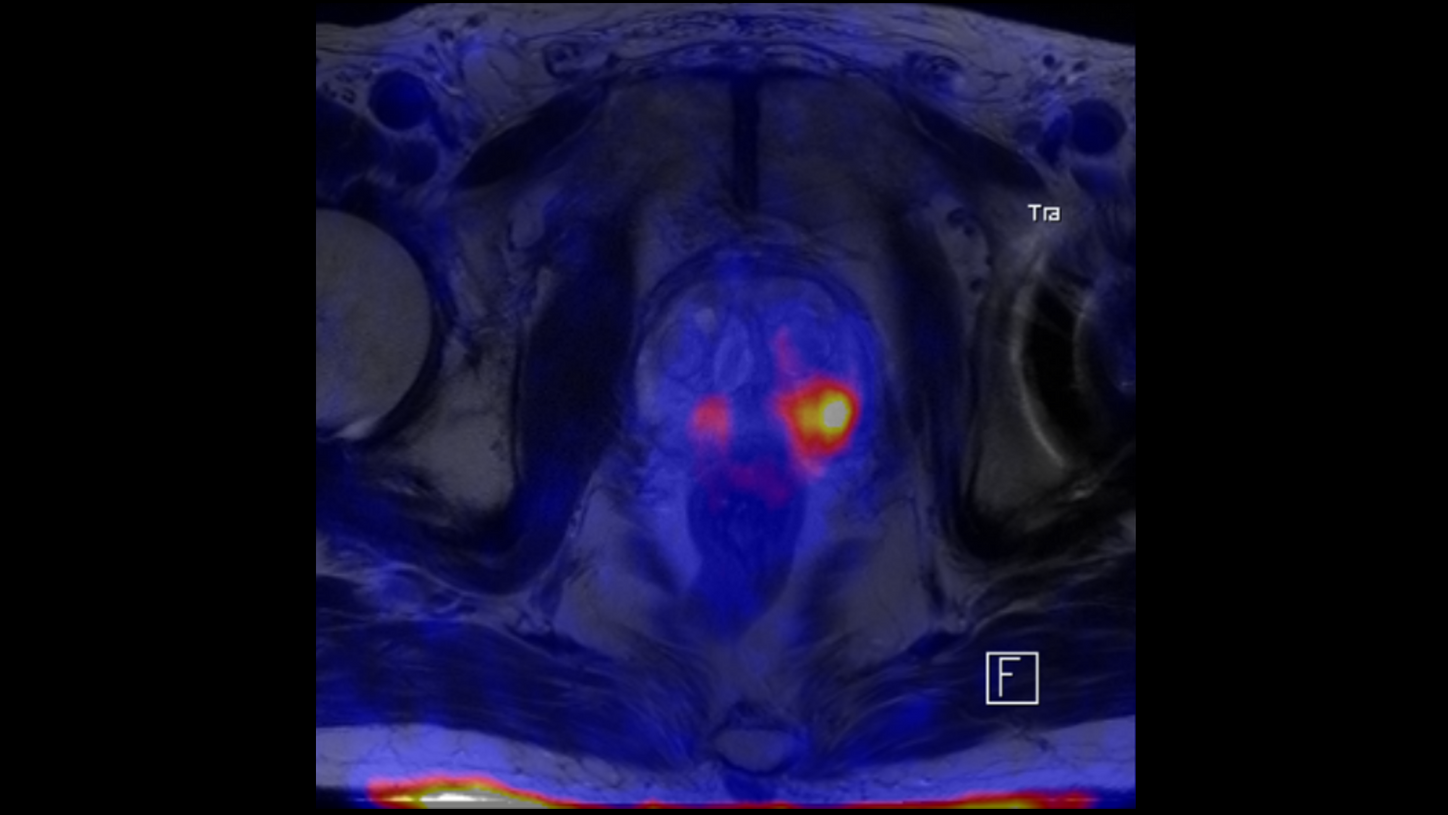

BIOGRAPH One is designed to excel in PET/MR precision to support confident diagnostic decisions. Featuring the Optiso UDR Pro detector with the largest 35 cm axial FOV2 in PET/MR, it is designed to enable comprehensive capture with excellent sensitivity and ultra-fast TOF3 in real time – delivering clear, detailed images.

Planned with Deep Resolve for accelerated acquisition and improved resolution in 2D and 3D applications4, BIOGRAPH One has the potential to make PET/MR exams faster than ever before. Designed with a powerful 3T magnet at its heart, BIOGRAPH One will deliver unparalleled performance with outstanding homogeneity, a large 55 x 55 x 50 cm³ field of view and robust gradient power.